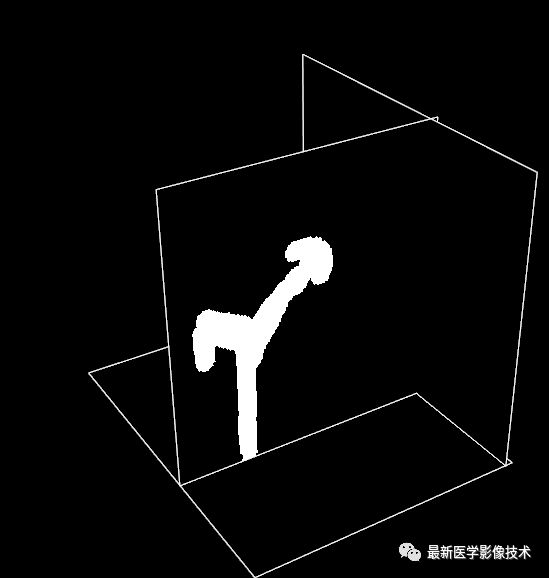

然后,在图像中的特定的一层,画出前景大致区域Mask并设置成255,其它区域为0,如图所示。